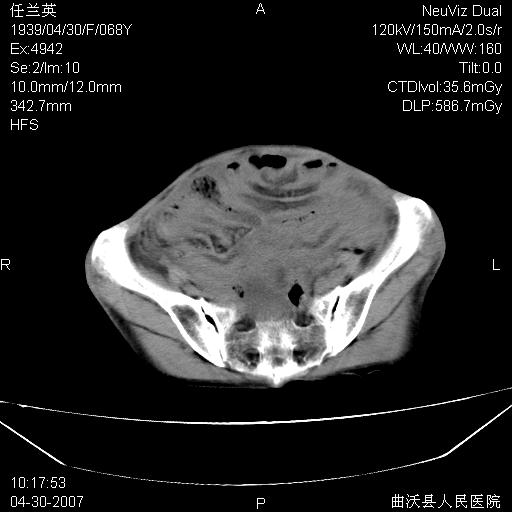

患者,女,68岁,感觉腹部憋涨发硬数天,查b超发现左盆腔有囊性肿物和少量腹水,行ct检查

1.考虑卵巢肿瘤并腹腔广泛性转移可能性大;

2.腹盆腔少量积液。

支持左侧卵巢恶性肿瘤伴网膜、腹膜广泛转移。

支持:左侧卵巢恶性肿瘤伴网膜、腹膜 腹膜后(淋巴结)广泛转移。

难的一见 典型 - 网膜饼  冰冻骨盆 可以当教学片了